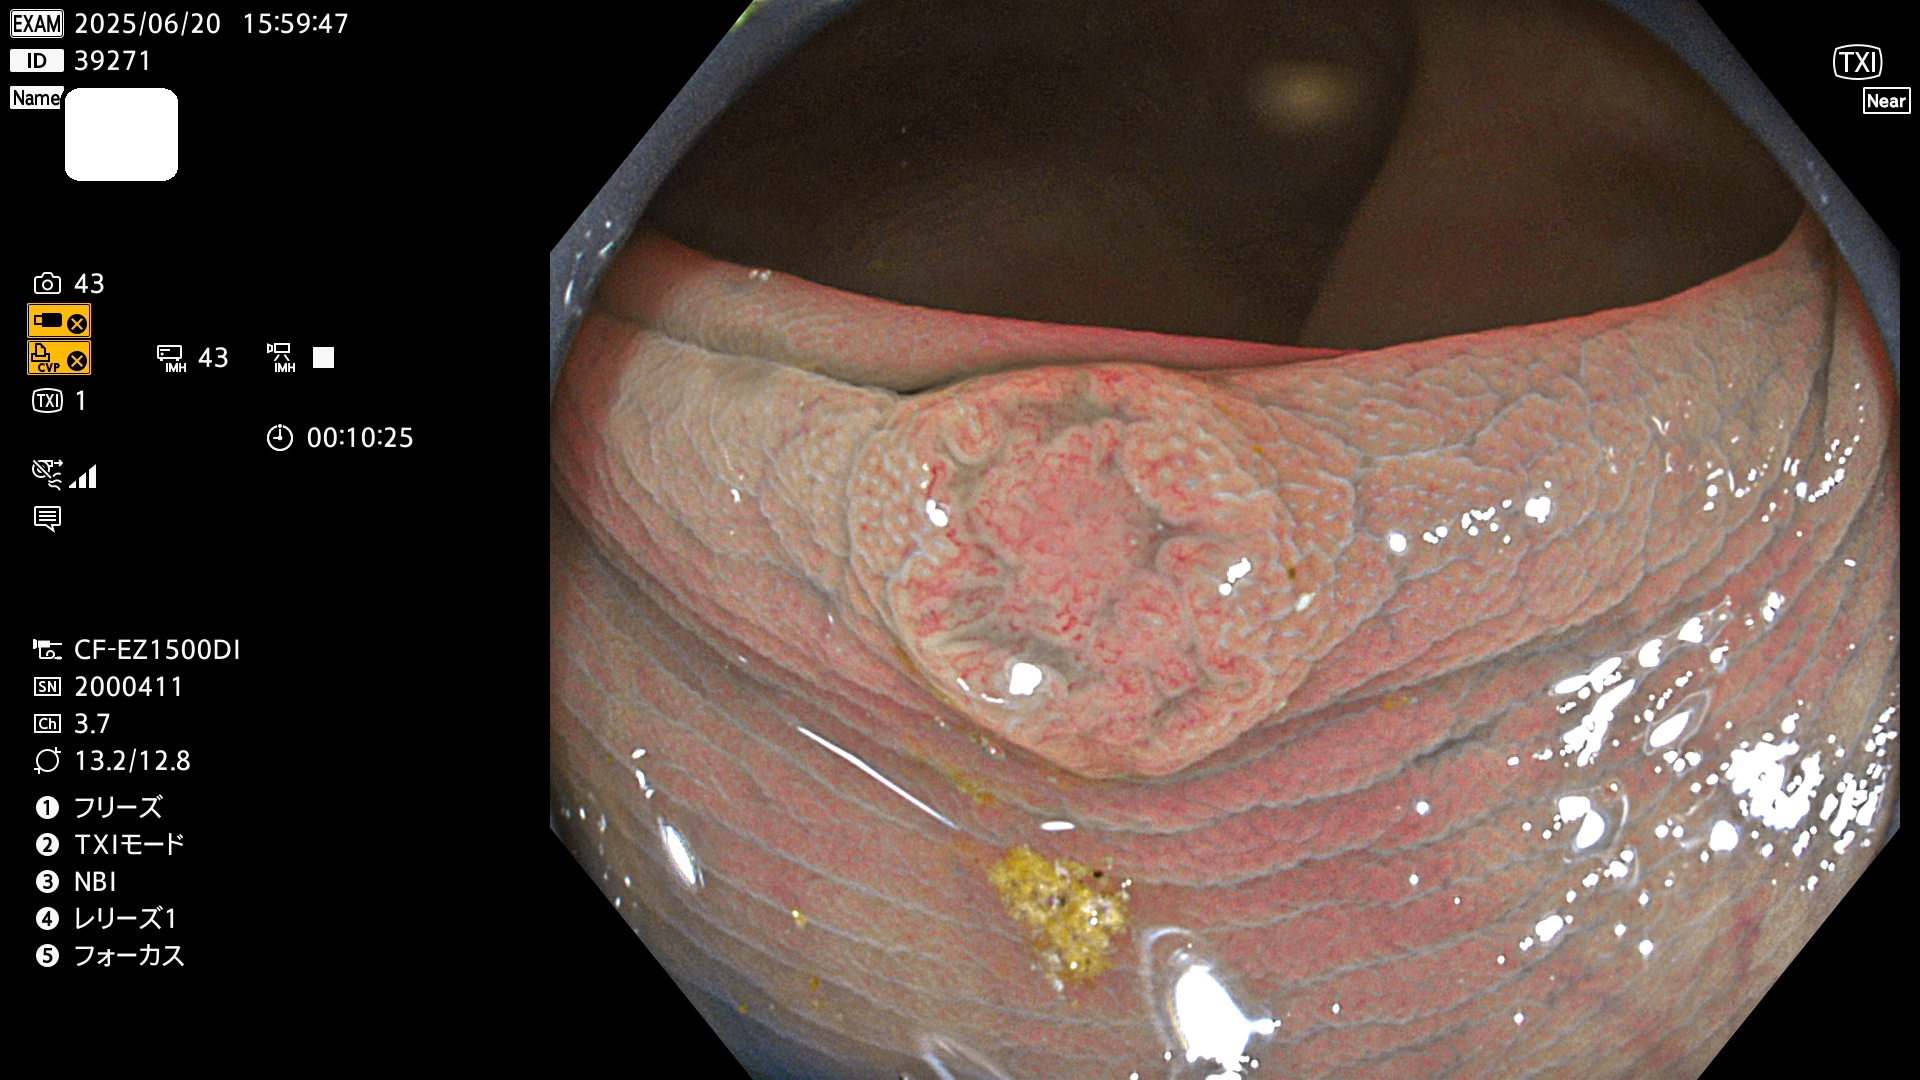

完全に平坦な物をUb、陥凹している物をUcと呼びます。Ubは認識が困難で、Ucはびらん(炎症)と紛らわしいために見落とされやすく、「内視鏡後・大腸癌」の原因になります。

抽出の対象期間 2025年6月19日〜6月22日の4日間(48件の検査)10個 (10/48=20%)